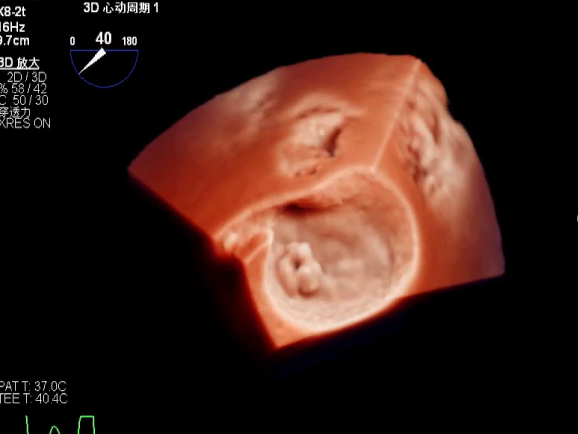

3D视图两个夹子近似并排排列,第二个夹子外侧小残余脱垂,瓣叶裂孔已不明显

3D证实夹子外侧残余脱垂及瓣叶裂空